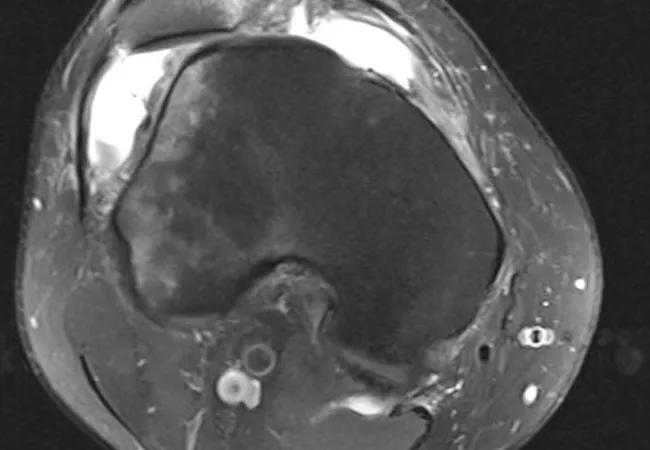

Figure 3. Patella alta. The inferior patellar cartilage (arrowhead) sits above the trochlear articular cartilage (arrow), demonstrating severe patella alta. Normally there is chondral overlap.